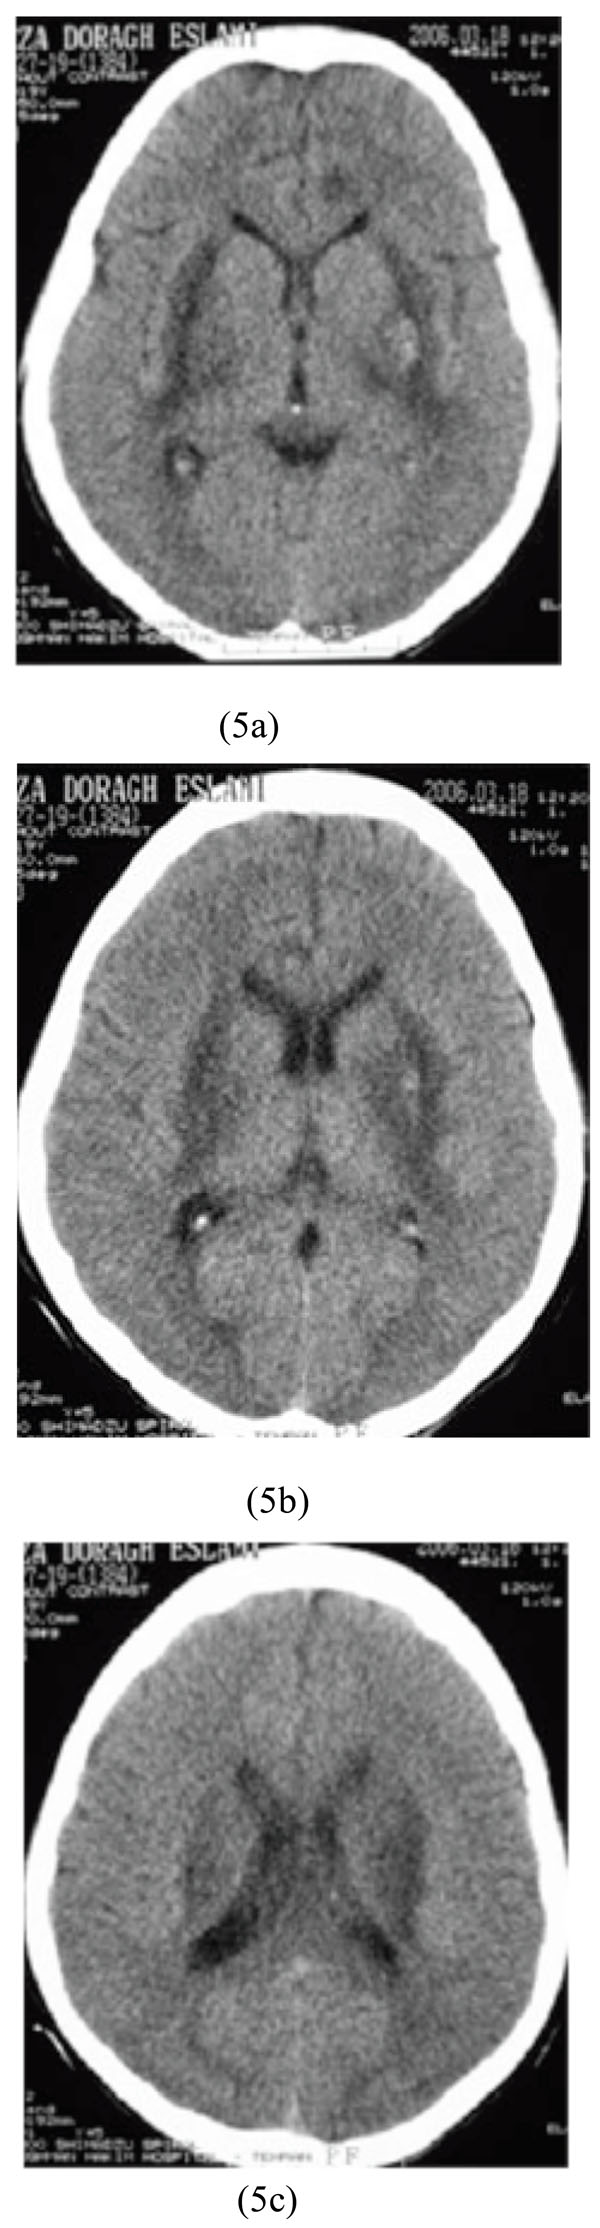

Diagnostic imaging is a valuable device in clinical management of poisoned patients presenting to emergency units in a comatose state. Some toxic agents have adverse effects on the central nervous system (CNS). Non-contrast computed tomography (CT) of the brain, as an available diagnostic method with a high resolution, can provide useful information about structural disturbances of unconscious patients with suspected drug or chemical intoxication. The authors would describe various presentations of toxic substances detected on the brain CT scans of ten patients with acute intoxication. While non-specific, CT findings of low-attenuation lesions in the basal ganglia, infarctions in young patients, or diffuse edema should raise suspicion for poisoning or overdose.

Non-contrast computed tomography (CT) of the brain, as a worthwhile radiological method, can guide the emergency staff to make a more accurate diagnosis and better medical management of unconscious patients with suspected drug or chemical intoxications. Cytotoxic edema and hpodensity lesions of the basal ganglia were the most common findings in this population. In our center, specific laboratory methods to detect various chemicals or drugs abused are not always available. Therefore, reported signs on brain CT scans presented in this article may increase the awareness of emergency radiologists, and also clinical toxicologists with respect to various neuroimaging findings of drugs and chemicals.

While non-specific, CT findings of low-attenuation lesions in the basal ganglia, infarctions in young patients, or diffuse edema should raise suspicion for poisoning or overdose.